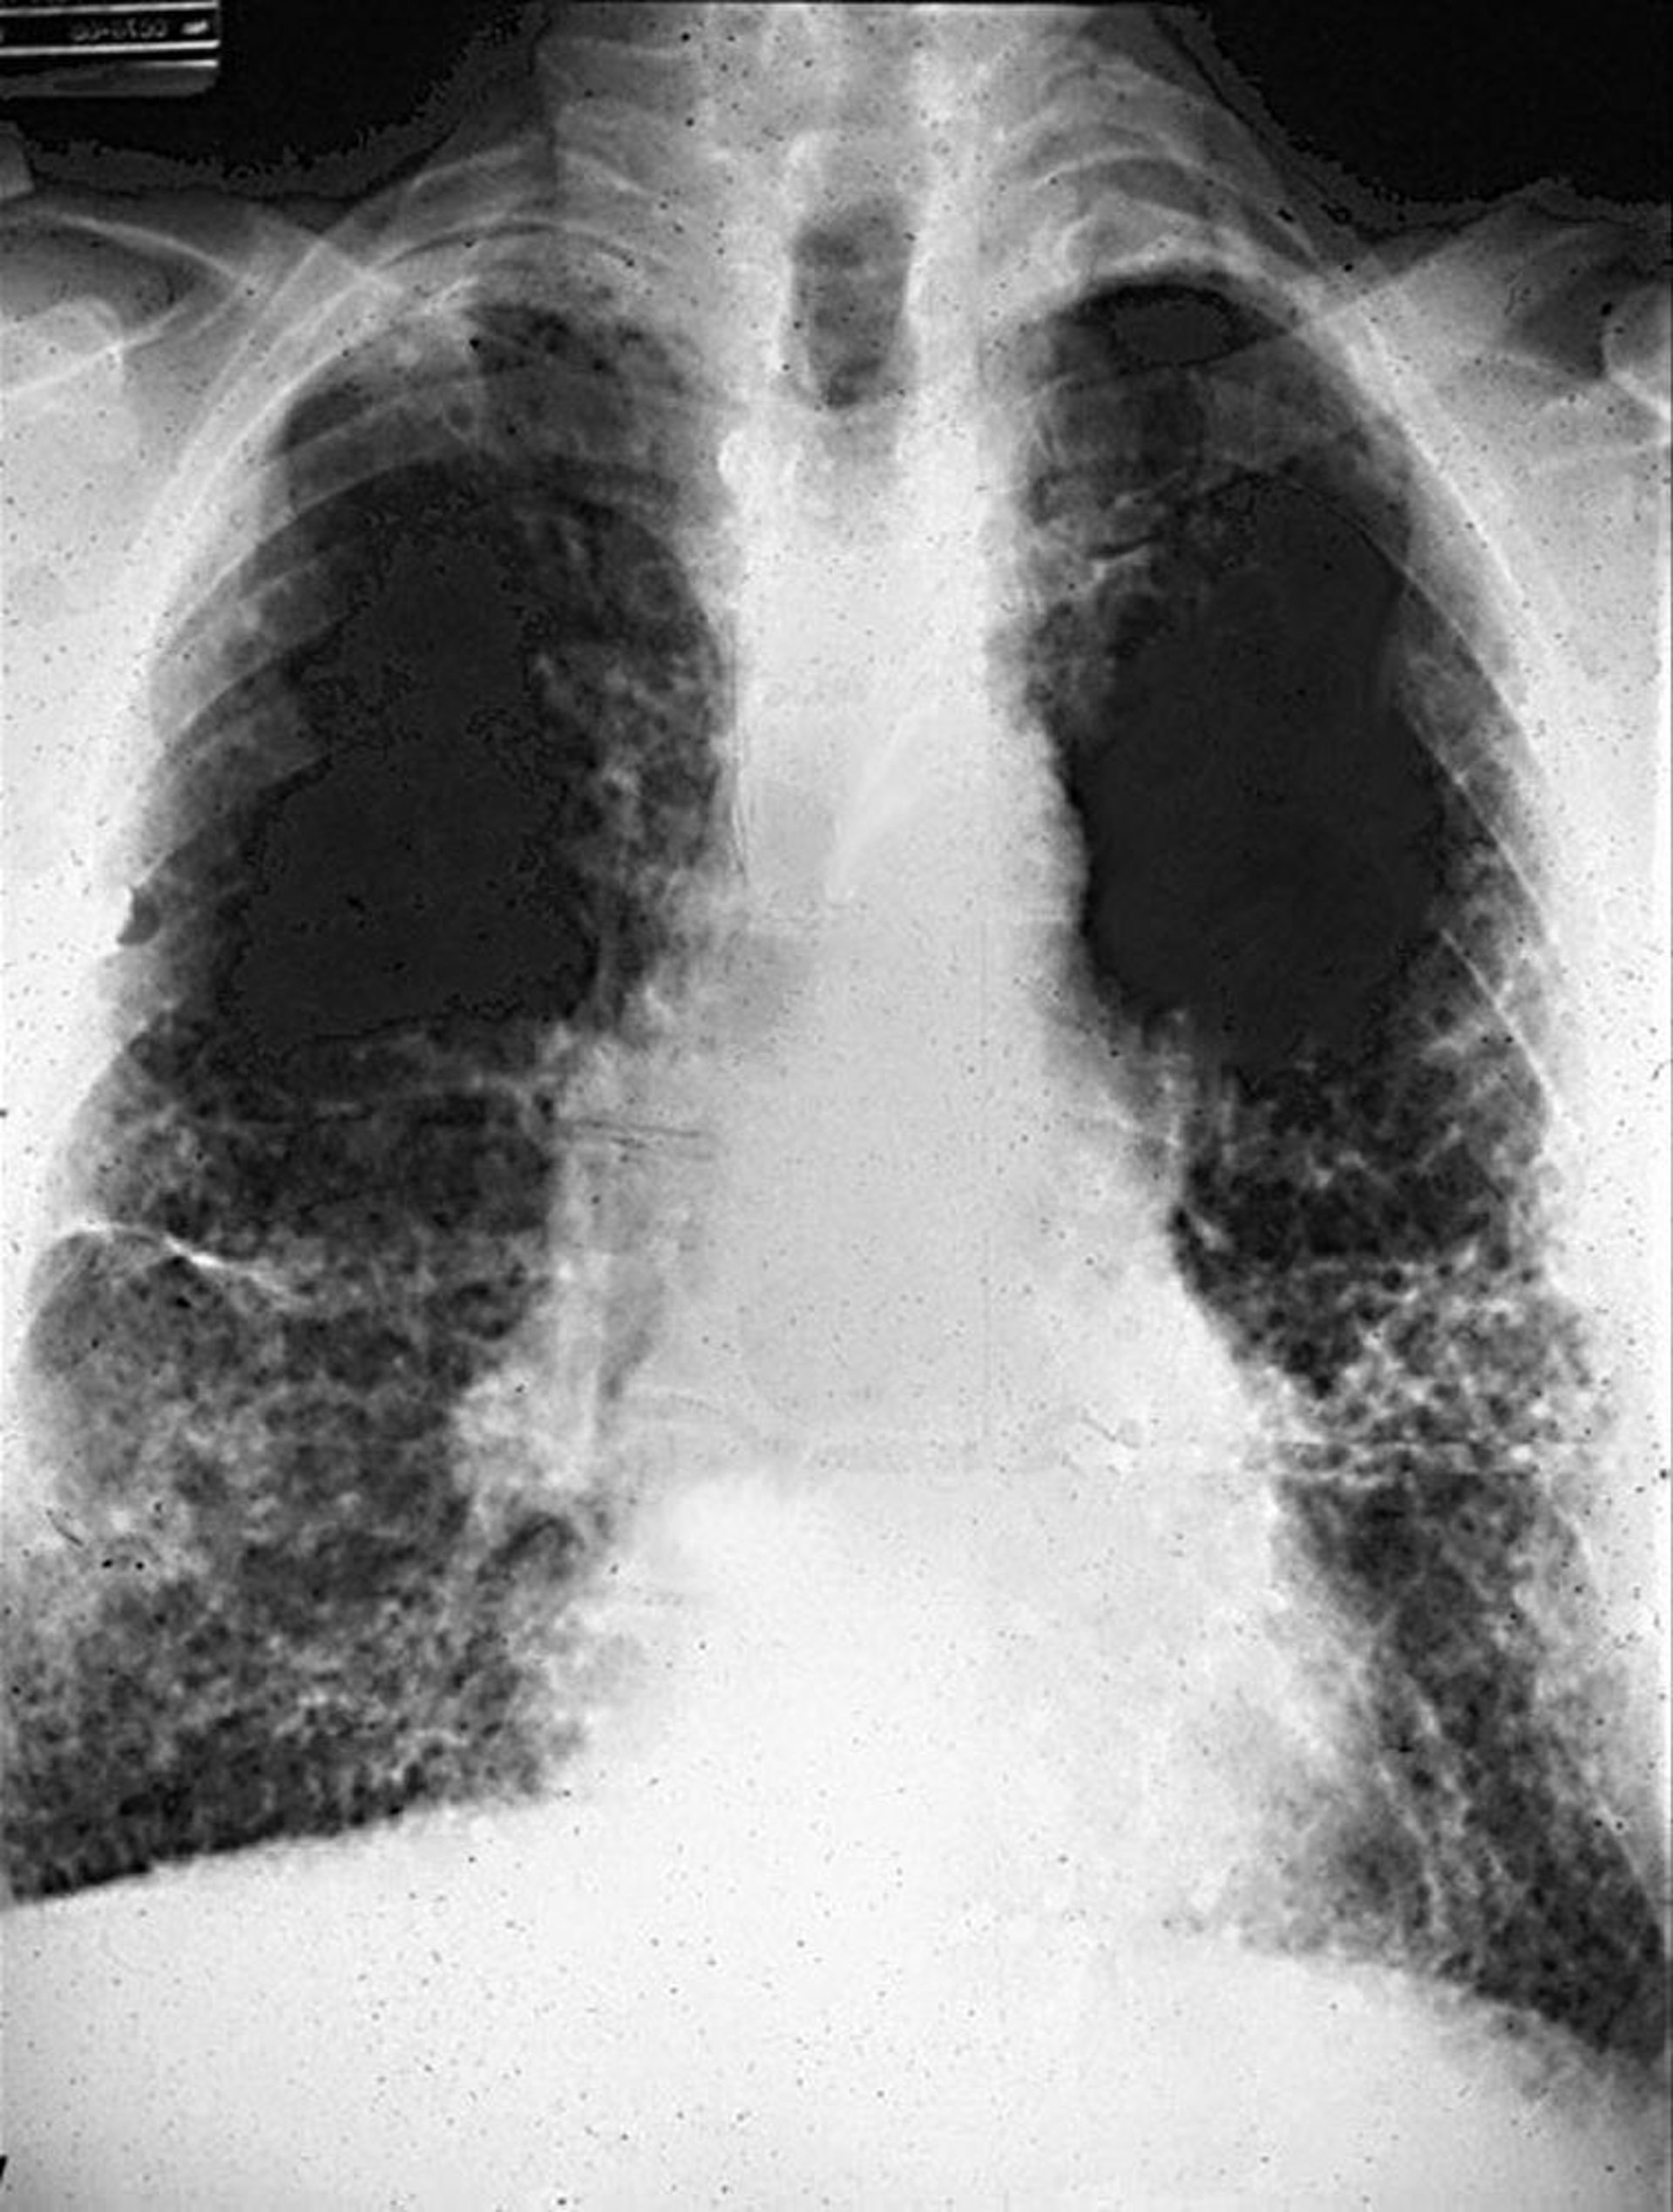

Modifications réticulaires avec nid d'abeilles dans l'asbestose.

Image courtoisie de David W. Cugell, MD.